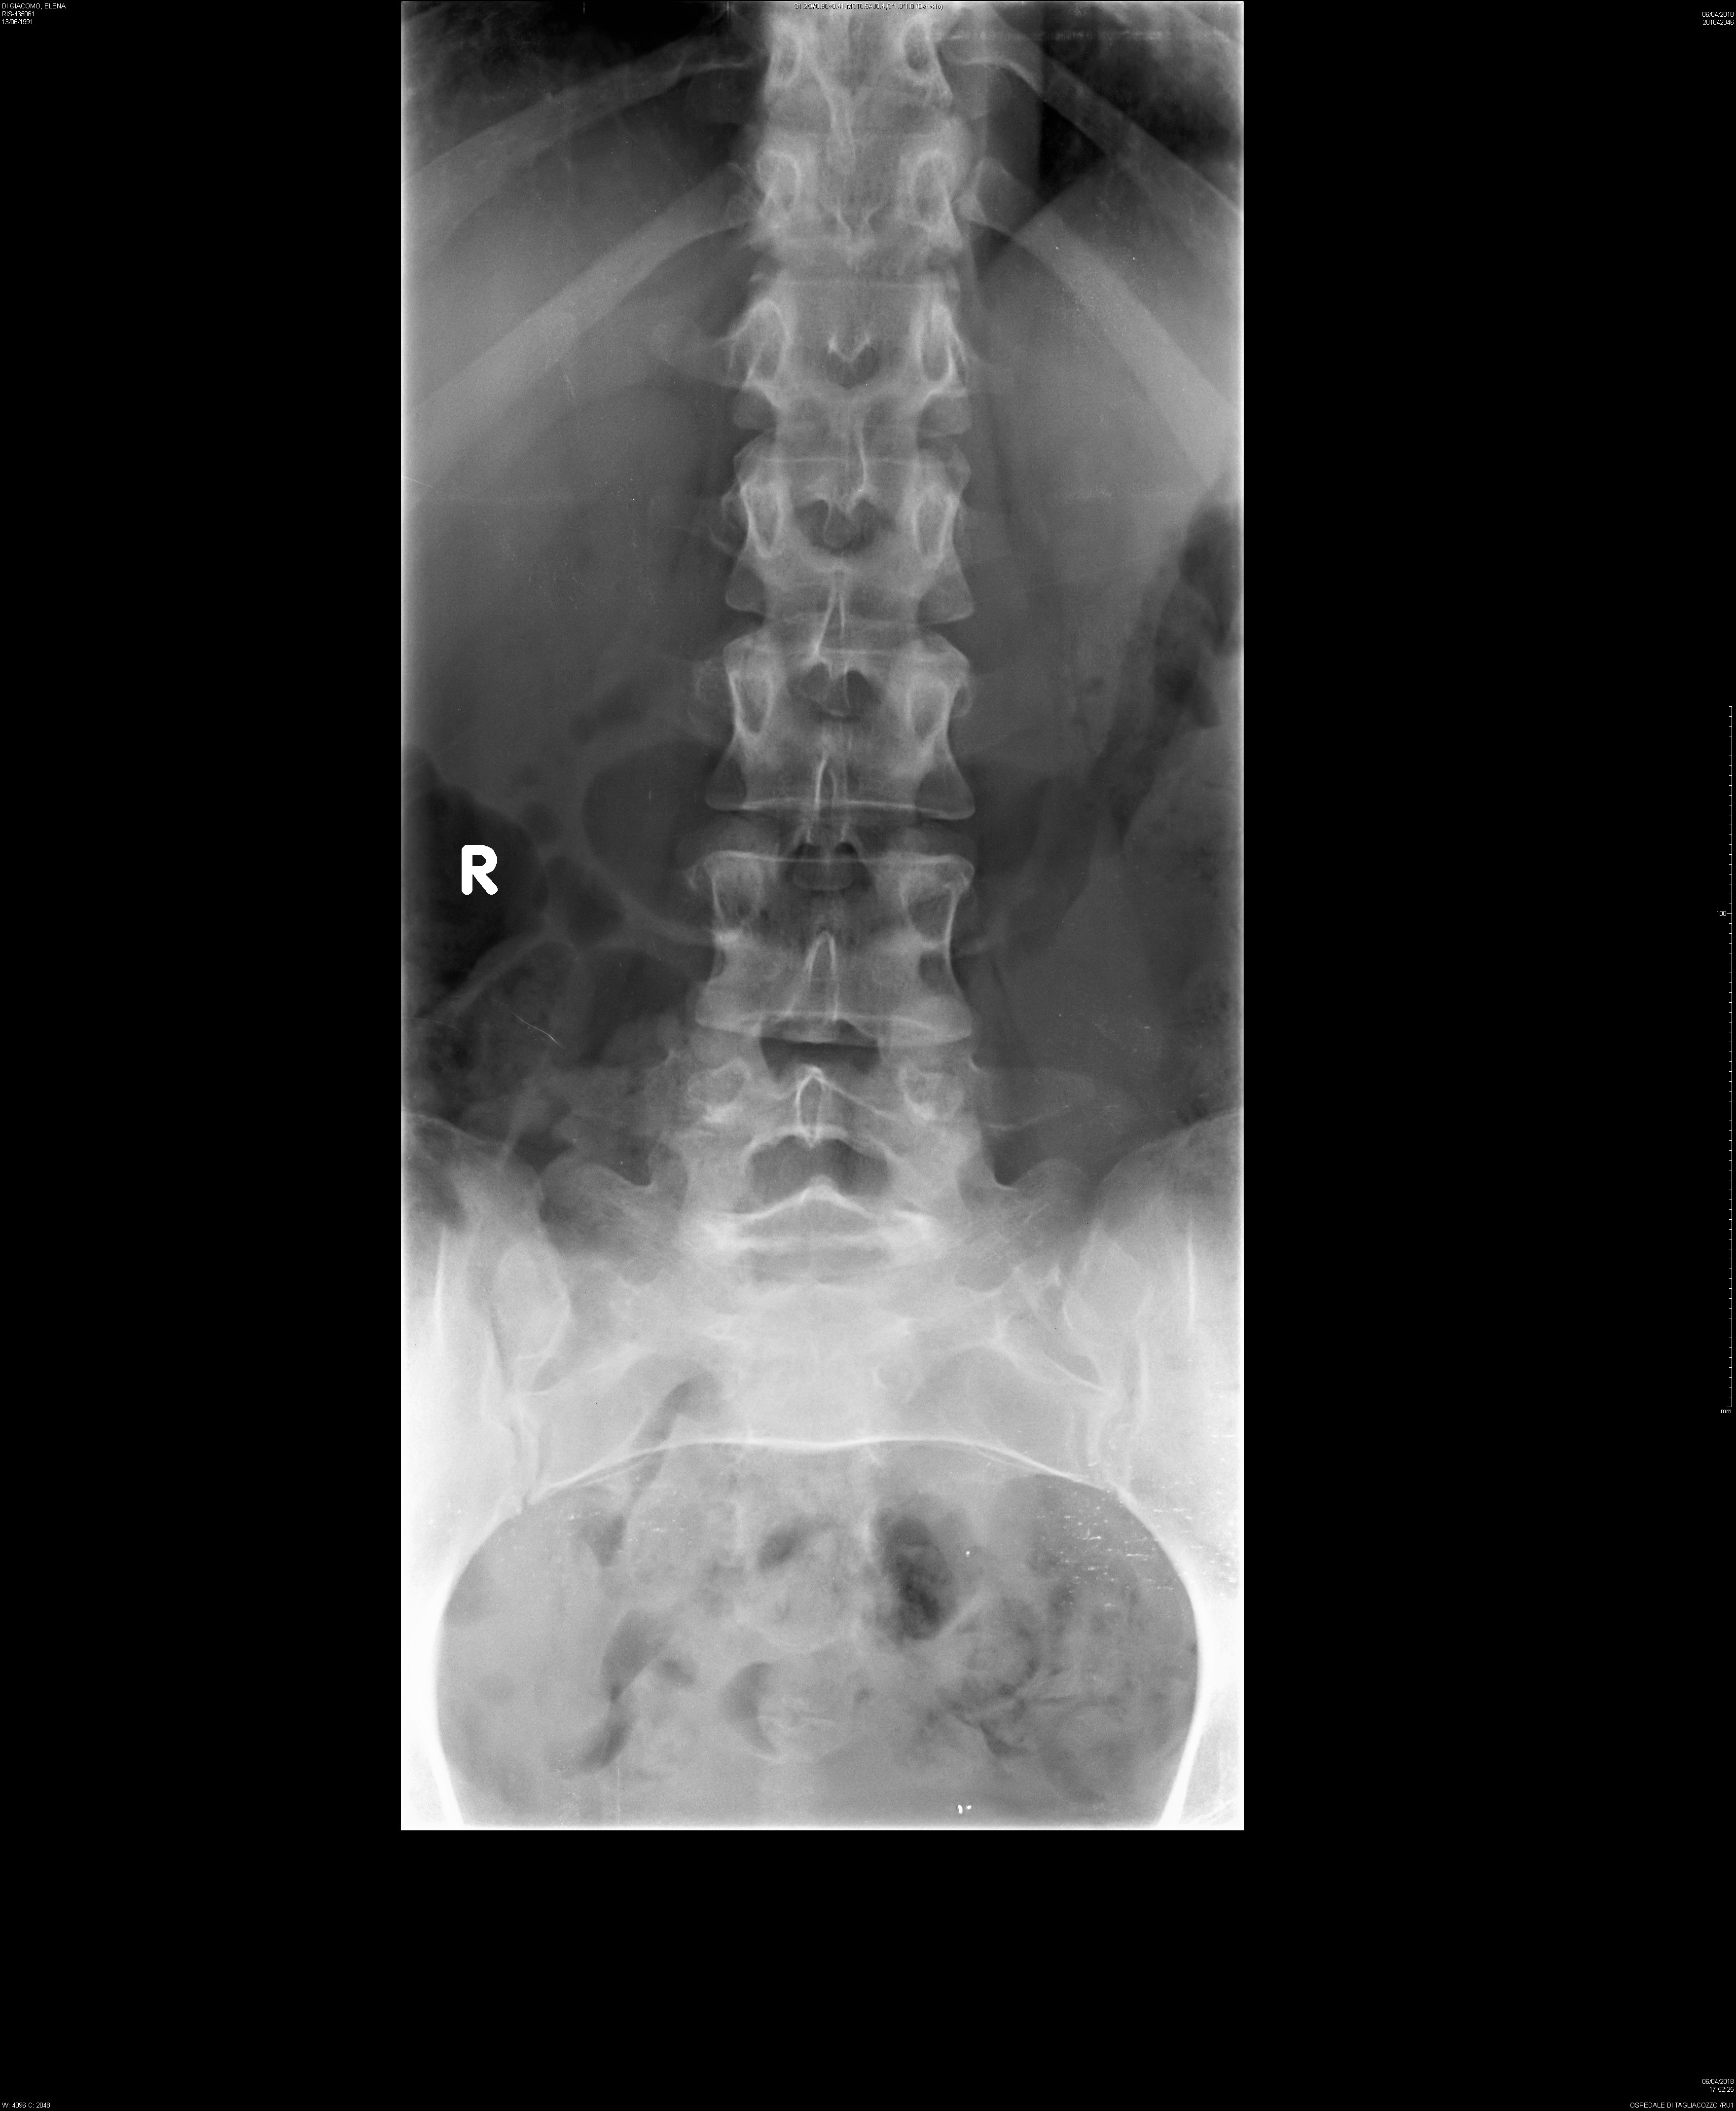

Salve, mi chiamo Elena, sono una ragazza di 27 anni e da circa un paio di anni ho un problema alla schiena. Il dolore è caratterizzato nella zona lombare , soprattutto nella parte sinistra, fino ad estendersi alla parte alta del gluteo sinistro.

Il medico, pensando fosse qualche infiammazione di qualche articolazione o altro, mi ha prescritto il ketoprofene per 10 giorni senza risulati. Così ho eseguito una lastra, le cito il risultato:

-Dismorfismo al passaggio LS per lombarizzazione di S1

-Riduzione d'ampiezza dello spazio discale L5-S1

-Rettilineizzata la lordosi lombare

-Non alterazioni morfostrutturali delle articolazioni coxofemorali

Il dolore/formicolio è persistente, delle volte durante qualche movimento rimango bloccata (soprattutto durante una camminata a passo sia normale che svelto), l'unico sollievo è stendermi supina, piegare le gambe e portarle fino al petto.